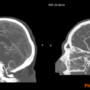

RadioMatrix radiopaque. Image via Stratasys.

The material has already been utilized in collaborative research projects in the UK with partners including CPI and Beaumont Hospital, demonstrating its potential in clinical and educational settings. Radiopaque 3D printed phantoms, such as cerebral angiography models, are helping improve training fidelity and create repeatable environments for imaging research.

Early findings from the Stratasys–Siemens Healthineers collaboration show that RadioMatrix phantoms can replicate human tissue with high accuracy in CT imaging, with deviations as small as a single Hounsfield unit (HU) in sensitive areas like grey matter and veins. Combining Stratasys’ Digital Anatomy technology with advanced imaging algorithms, the resulting models maintain anatomical and pathological details while providing a consistent, ethical alternative to cadaver-based training.